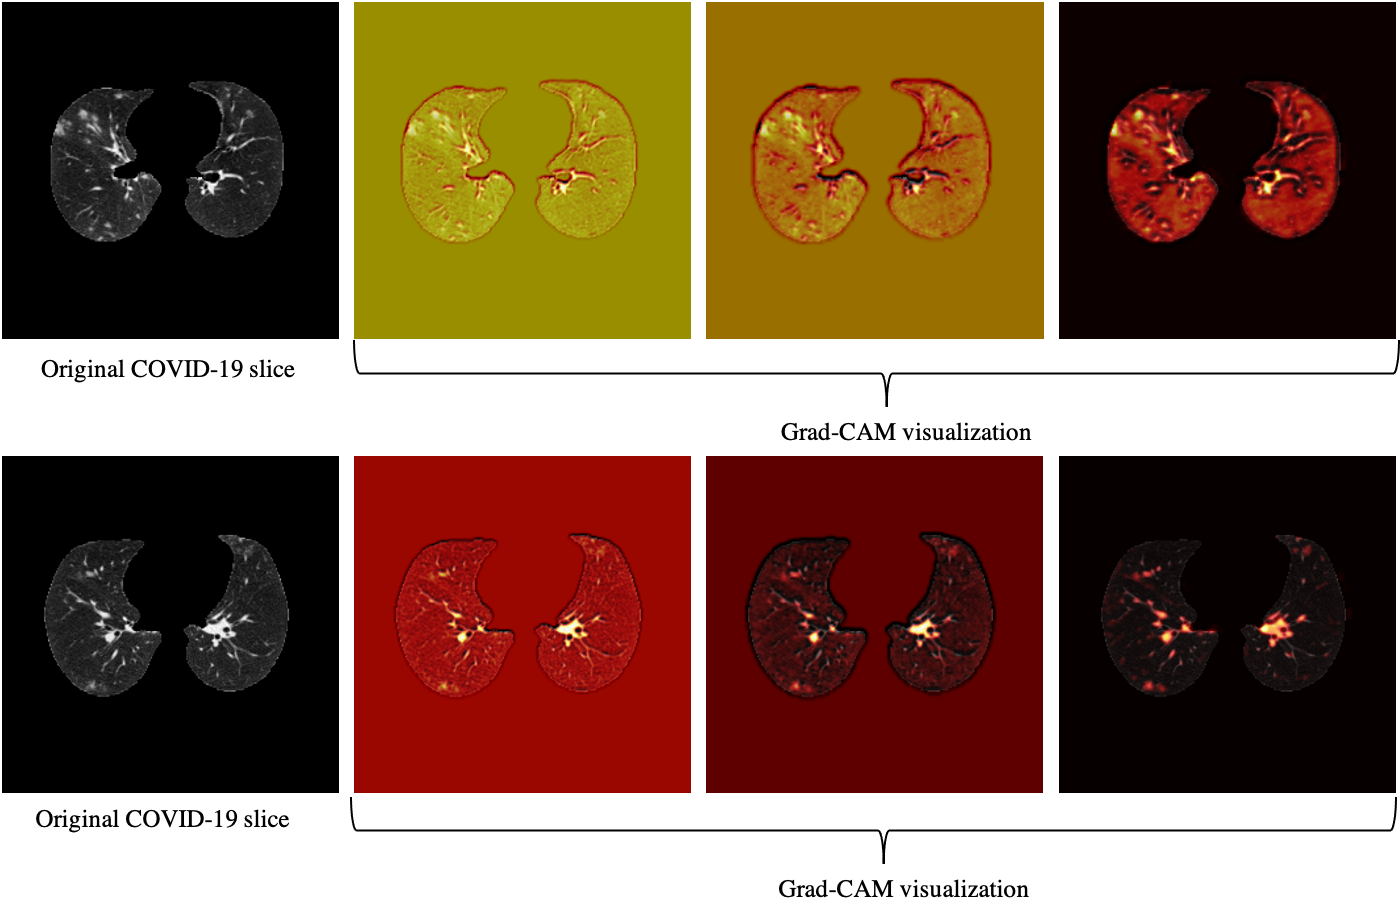

Refer to caption

Figure 5: Grad-CAM visualization of two COVID-19 slices. This figure shows that the proposed AI model is paying attention to relevant locations of the image.

Based on the CT scans only, we analyzed the misclassified COVID-19 cases through all folds (11 cases in total), and studied their relation with the disease severity, coming to the conclusion that 4 out of 11 cases, did not have any related imaging findings, 5 were scored 1 by the three radiologists, one was scored 2, and only one case was scored at 3, which means the developed model is less likely to misclassify severe cases. Neither the developed model nor the experienced radiologist was able to detect the 4 COVID-19 cases without imaging findings, using CT scans only. Furthermore, since the CAP patients come from a different cohort and scanned with a standard dose, we visualized the model’s output for CAP cases, one of which is shown in Fig. 4, using Grad-CAM localization technique. This figure shows that the model is paying more attention to disease-related regions of the image, rather than dose-related ones. We performed the same localization technique on two slices with infection of the same COVID-19 patient, shown in Fig. 5.

Grad-CAM Visualization

We utilized the Grad-CAM localization mapping method [36] to provide a deep insight into the intermediate layers and identify what components in a CT image have obtained the most attention by the model. The Grad-CAM method extracts the spatial information, which is preserved by the convolutional layers and specifies the parts in the image having the most contribution to the final prediction. More specifically, the Grad-CAM method generates a localization heatmap corresponding to each layer and the target class to determine the locations to which the model paid the most attention. This localization heatmap is derived by a weighted average of all feature maps in the convolutional layer followed by a Rectified Linear Unit (ReLU) activation function.

Our study has some other limitations. First, the dataset is collected from a single centre, and experiments are required to verify its performance on data from external institutes, as it is critical to investigate if the model generalizes to diverse population [28, 29]. Vulnerability to data shifts, and bias against underrepresented population [28] are also crucial to address before the AI model can be put into practice. It is worth mentioning that as the extra set of 100 positive COVID-19 patients are collected in a disjoint time interval from the original set, it can act as a narrow validation [29]. It is, however, collected from the same institute and thus does not account for broad validation. It is also of high interest to explore domain validation for COVID-19 diagnosis, where test set comes from different variants. Second, the sample size is relatively small. Verifying the model’s performance on larger multi-centre datasets is the goal of our upcoming studies. The capsule network used in our study, is capable of handling small datasets compared to conventional models and due to fewer trainable parameters it is less prone to over-fitting, however, larger datasets can still improve the performance of the model. We also aim at expanding the proposed AI model to predict the disease severity besides the diagnosis. Moreover, although as shown in Figs. 4 and 5 visualization of the AI model’s output shows it is paying attention to relevant regions, more research is required to increase its explainability. Low performance on COVID-19 cases without imaging finding is another limitation of the developed model.